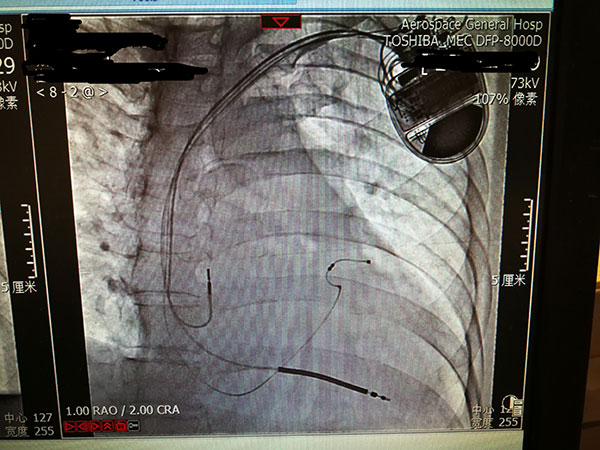

7月29日,總醫(yī)院的一位住院患者突發(fā)惡性心律失常,心率達(dá)到263次/分,危在旦夕??傖t(yī)院啟動應(yīng)急預(yù)案,開啟綠色通道,成立了專家小組,由戴天然院長親自指導(dǎo),心內(nèi)科李茂榮主任和甘豐副主任具體負(fù)責(zé)。為搶救患者生命,專家小組在幾經(jīng)討論,充分和家屬溝通后,果斷決定對患者采取植入式再同步心律轉(zhuǎn)復(fù)除顫器的手術(shù)。隨后總醫(yī)院多科室迅速聯(lián)動,在最短時間內(nèi)為患者安排了手術(shù),克服重重困難為患者成功植入除顫器,現(xiàn)在患者情況恢復(fù)良好,已準(zhǔn)備出院。